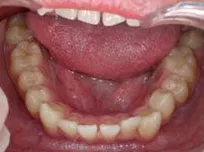

以下、当院で実施した床矯正の症例となります。

症例1

| 治療期間 | 11ヶ月(2021年6月〜2022年5月) |

| 費用 | 495,000円(税込) |

| リスクや副作用 | 成長期が終わった18歳以降に、2期矯正が必要になることがある |